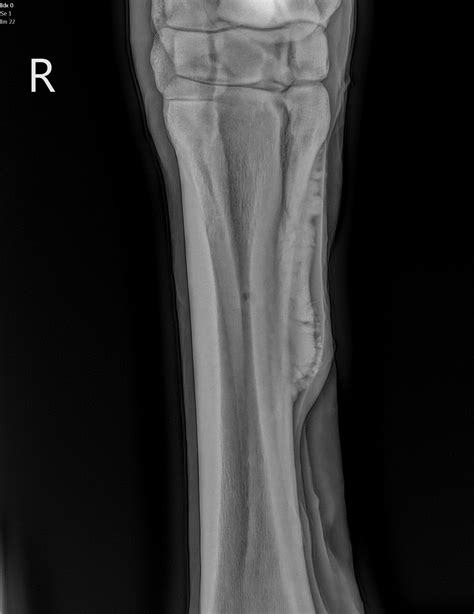

A fractured or broken bone is always considered a traumatic injury, but not all are classified as serious — there are different types based on severity. A break in a bone usually caused by a fall. Splint bone fracture usually results from one of the following:

Musculoskeletal injuries are common in professional athletes and. More common are the front cannon fractures but there are also hind cannon fractures often caused. Fractures of the splint bones can occur anywhere along their length, but are most commonly located at the lower third. Condylar fracture of the cannon bone is most commonly seen in racing thoroughbreds. A hairline or stress fracture of bone is the least. He is a 10 year old off the track race horse and had a previously fractured cannon bone from racing. A broken bone is a fracture. Plates are placed on the tension side of the bone note plate positioning. The cannon bone is the large bone in the lower leg which runs from the knee down to the ankle. While mild strains and sprains of ligaments and muscles can often be treated at home, fractures typically require professional medical care. There are different types of fractures and symptoms include pain, swelling, and discoloration of the skin around the injured broken bone (types of bone fractures). Fracture of cannon bone, condylar. Although most of the research on these. Cannon, ulna, femur, tibia, complications, exfix t/f: A fracture, simply put, is a broken bone. .span the whole bone to not create a stress. Great efforts applied used plates & screws to manage the fracture.